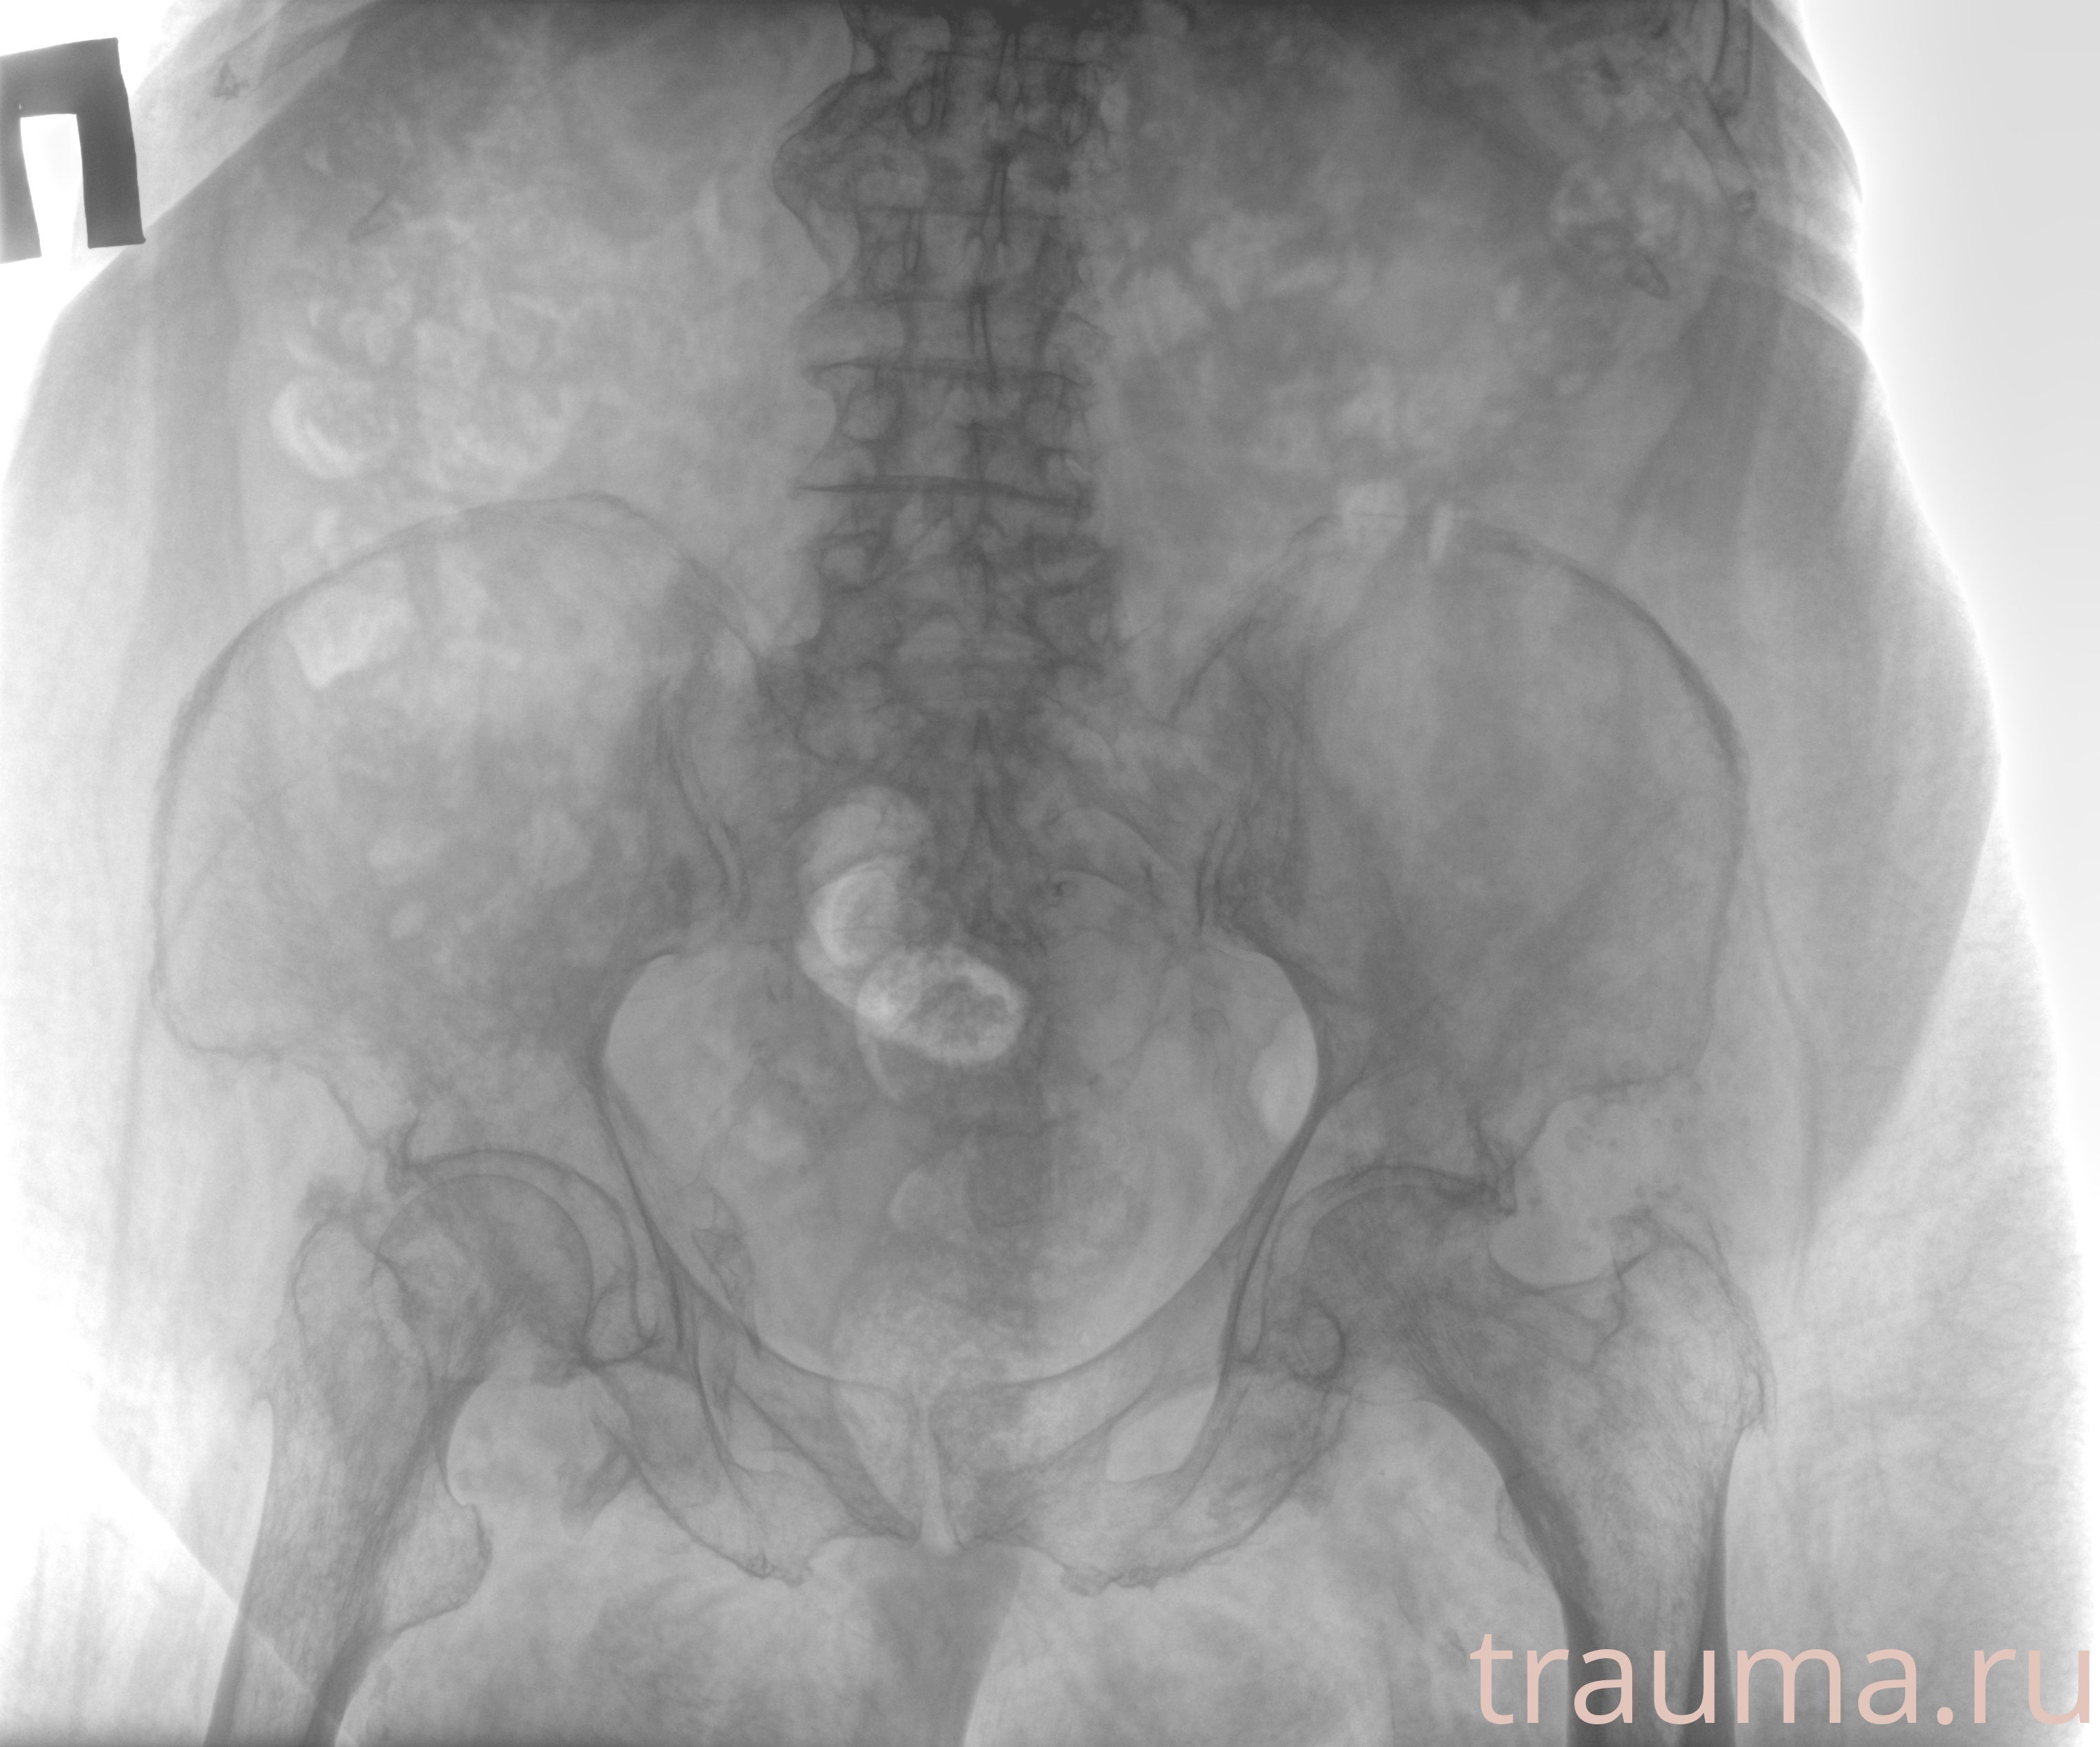

Рентгенограммы

Рентген на дому: по вашему адресу приезжает врач-рентгенолог, травматолог-ортопед с мобильным рентгеновским аппаратом, проводит диагностику травмы или заболевания, делает необходимые рентгенограммы, дает рекомендации по дальнейшему лечению. Получить качественные снимки в домашних условиях возможно благодаря уникальной методике, разработанной МосРентген Центром для института  Склифосовского

при переломе шейки бедра и пневмонии от компании МосРентген Центр - партнера Института имени Склифосовского